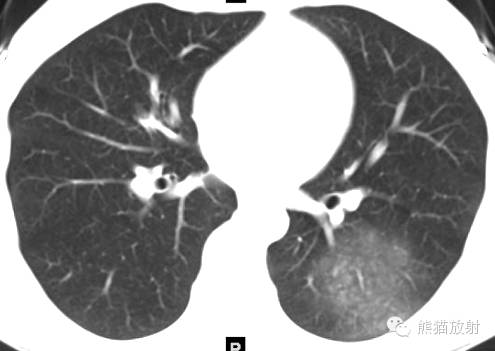

女,19岁,每次来月经时咯血。

CT诊断:结合病史,考虑左下肺子宫内膜异位症(渗出型),建议月经间期复查。

诸病灶分别如下图中圆圈所示: